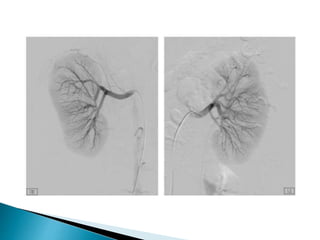

I.V. catheter is threaded through the femoral and iliac

arteries into the aorta or renal artery.Contrast material is

injected to visualize the renal arterial supply.

Evaluates blood flow dynamics, demonstrates abnormal

vasculature, and differentiates renal cysts from renal

tumors.

May be done to embolize a kidney before nephrectomy for renal

tumor.